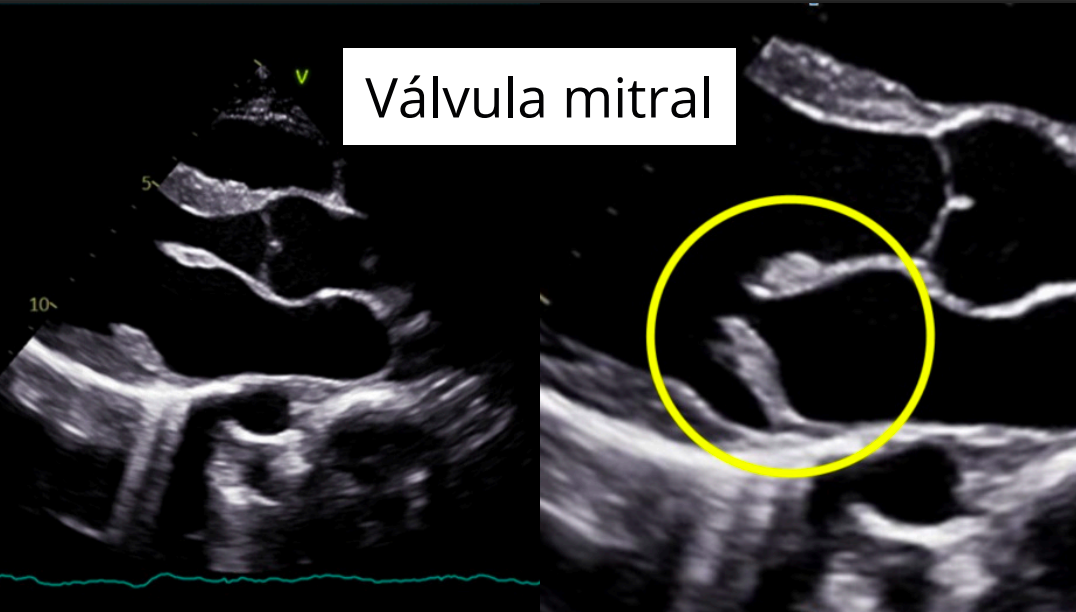

Enfermedad valvular mixomatosa mitral

- Degenerativa y progresiva.

- Afecta la válvula mitral, que se engrosa y deforma por acumulación de material mixomatoso.

- Provoca regurgitación mitral, con flujo retrógrado hacia la aurícula izquierda durante la sístole.

Hallazgos ecocardiográficos

- Regurgitación mitral (Doppler color).

- Engrosamiento y prolapso valvular.

Engrosamiento de las valvulas